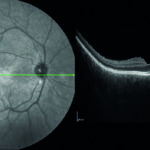

Una cefalea da indagare: diagnosi di sindrome di Vogt Koyanagi Harada